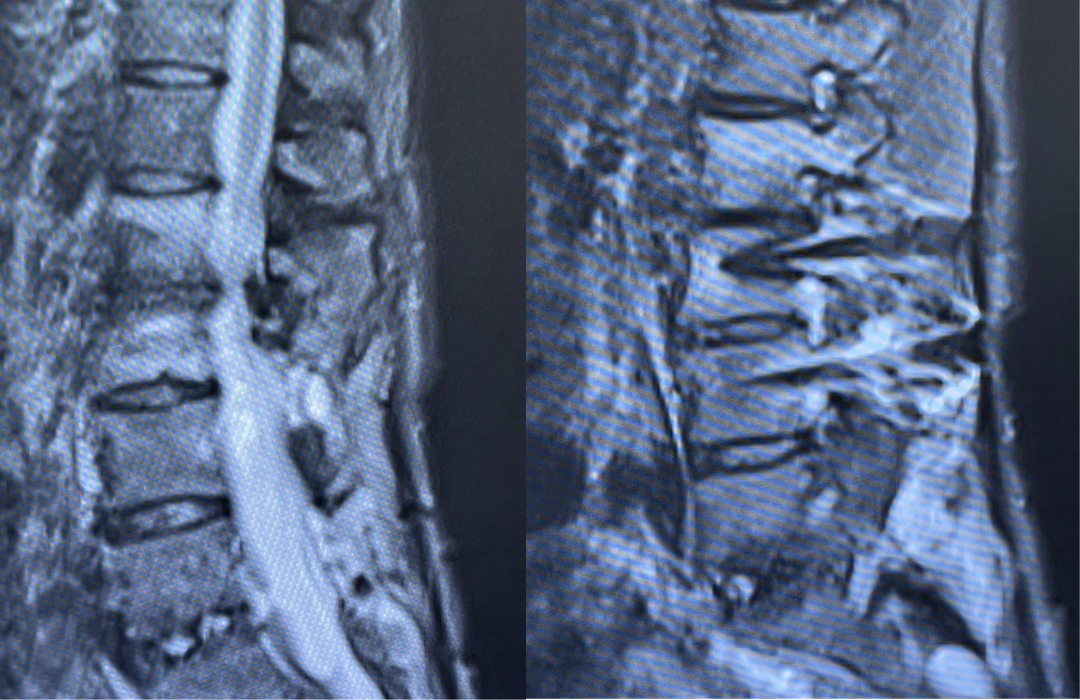

This 62-year-old female presents with chronic intractable low back pain with radiation down the front of her thighs. The patient had had two prior fusion surgeries: She initially had an L4-S1 fusion twelve years prior and a subsequent revision extension of her fusion at L3-4 that she had three years prior. She had a long-term history of smoking. She had mild hip flexor weakness, right greater than right. Imaging studies revealed next segment degeneration and stenosis at L2-3. (Figs. 1a and 1b and 2).

Figures 1a and 1b. Sagittal T2 MRIs of the lumbar spine demonstrating L2-3 stenosis after L3-4 instrumented fusion.